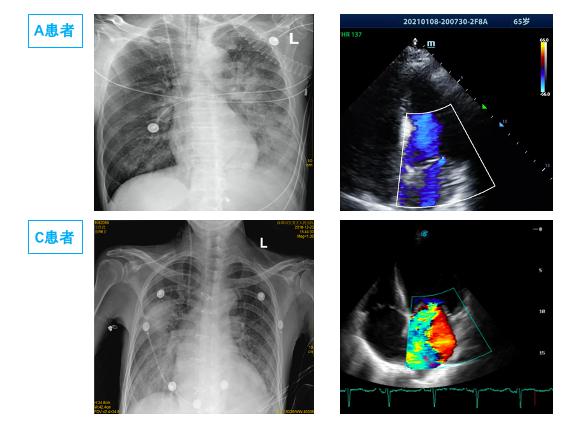

图 3 单侧PE患者胸片及二尖瓣反流 Fig 3 X-ray and mitral regurgitation of Unilateral PE

由于单侧PE病情轻重不一,影像表现可以为间质B线、毛玻璃影,严重可表现为肺实变,因此常误诊为肺部感染、肺出血、支气管扩张、肺实变等[29-31]导致病情延误。本研究中有12例单侧PE患者初次影像报告未准确识别; 因此建立重复可量化的单侧PE影像定义及分级标准有组于单侧PE诊断[32]。有心脏病史,心脏超声提示长期二尖瓣反流,长期有右侧胸腔积液,结合入院后床边BNP及肺部超声可以进行鉴别,尤其是床边重症超声可以及时发现明显二尖瓣反流,及时监测肺部超声表现可予以鉴别诊断。如图 4中B患者,入院前肺部CT正常,因失血性休克导致心脏骤停3 h后胸片提示右侧渗出加重,肺部超声由A线为主逐渐发展为B7线、B3线、融合B线及肺实变,提示患者PE程度逐渐加重; 同时心脏超声提示新发重度二尖瓣反流,综合考虑诊断单侧PE,经呼吸支持,利尿治疗后患者胸片、肺部超声均迅速恢复正常。而长期心衰合并二尖瓣反流患者,联合下腔静脉、颈静脉等超声进行容量评估,可与肺部感染相鉴别[33]。急性胸痛患者肌酸激酶同工酶联合床边及时检测肌钙蛋白,可早期诊断心肌梗死,为诊断心源性PE提供依据,本研究中两组间心肌损伤标志物差异无统计学意义。